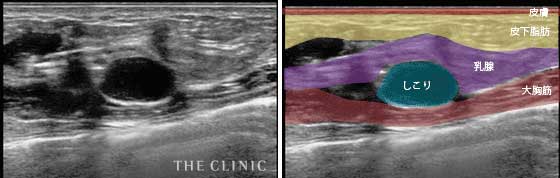

- しこりの位置

- 乳腺組織内にしこりができてしまった症例